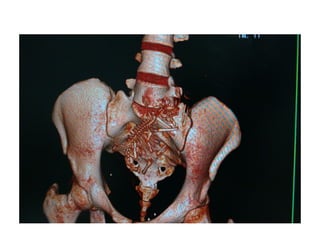

Varredura da Pelve

• Os limites são definidos pela extremidade

superior da crista ilíaca até a extremidade

inferior do ísquio.

• Os pacientes devem ser posicionados em

decúbito dorsal sem angulação do gantry.